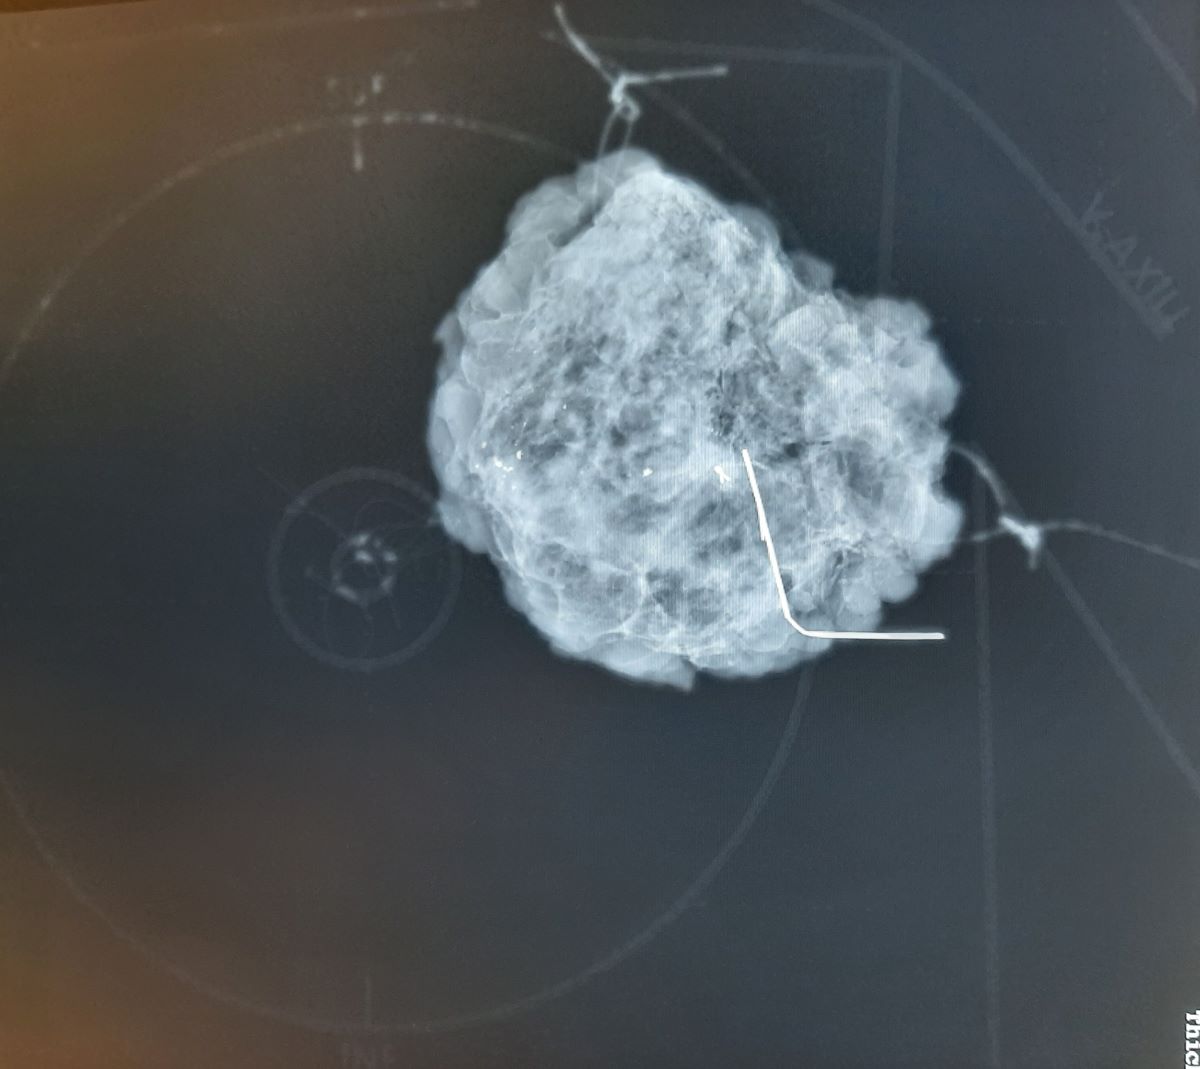

Figure 5. The mammographic image of the oriented breast tissue specimen with wire guide tumor localization on the specimen plate. The additional information of the plate is the high fidelity localization of the specimen within the breast. The traditional suture marking (long = lateral; short = superior) is also used with a thick yarn that creates an x-ray shadow.

In order to meet the above detailed requirements, a 3D printed (Appendix A) plastic specimen plate was built (Figure 2, Figure 3, Figure 4 and Figure 5), which allows the oriented anchoring of the breast tissue specimen representing the original in vivo situation. This way the removed specimen is completely consistent with the original layout in the patient. The plate is made to mimic the female breast and axillary scheme so that the location and direction of the specimen can be unambiguously determined.

This scheme can be clearly seen in mammographic images, but the plate does not have a disturbing X-ray positive shadow (Figure 3 and Figure 5). This plate provides mammographic images of breast specimens in the coronal plane, which is easier to understand and more dependable for surgeons and pathologists.